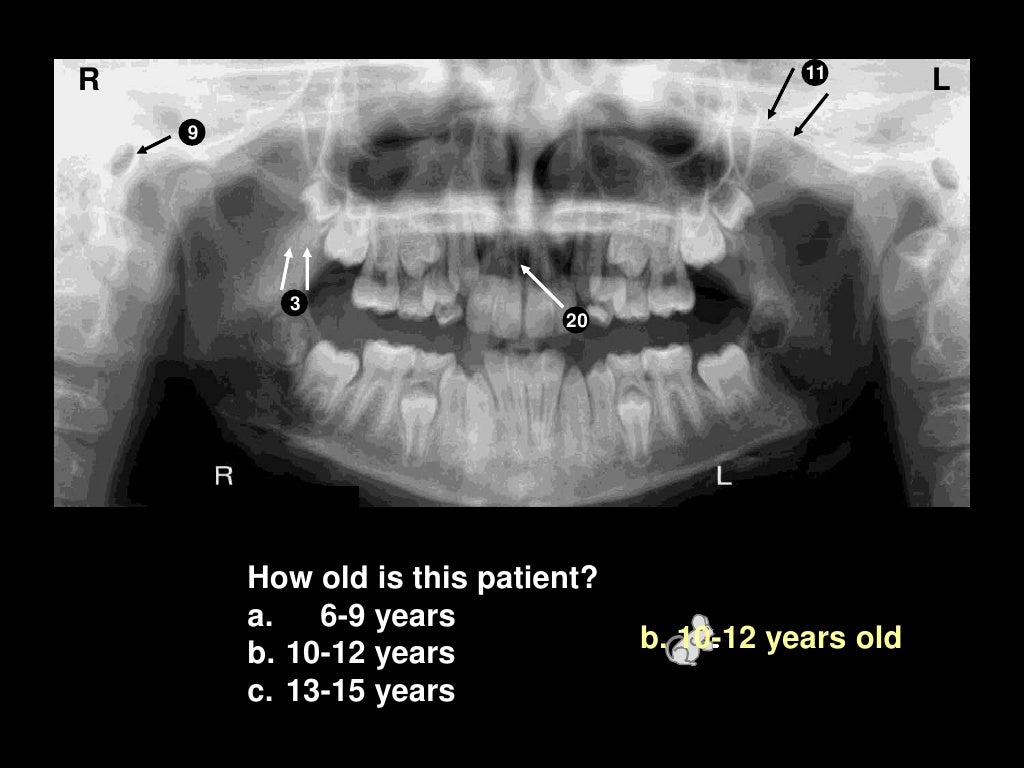

Radiographic AnatomyPAN Diagram Quizlet Pan- Definition Anatomy Prefix meaning all, entire (properly affixed to words derived from g. 110 rows understanding medical words: They help to avoid any ambiguity that can arise when describing the location of. Here is a list of word parts. Word parts and what they mean. Identify three planes most commonly used in the study of anatomy. It’s a complex assemblage of bones. Pan- Definition Anatomy.